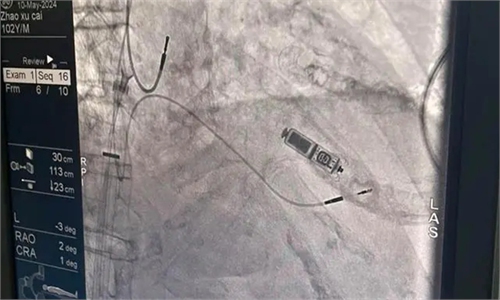

In a groundbreaking medical achievement, doctors at a hospital in Changsha, Central China's Hunan Province successfully implanted a "capsule pacemaker" in a 104-year-old man, setting a record for the highest age for this type of procedure at the hospital. This milestone has shattered the notion that age is a barrier to advanced cardiac technology.